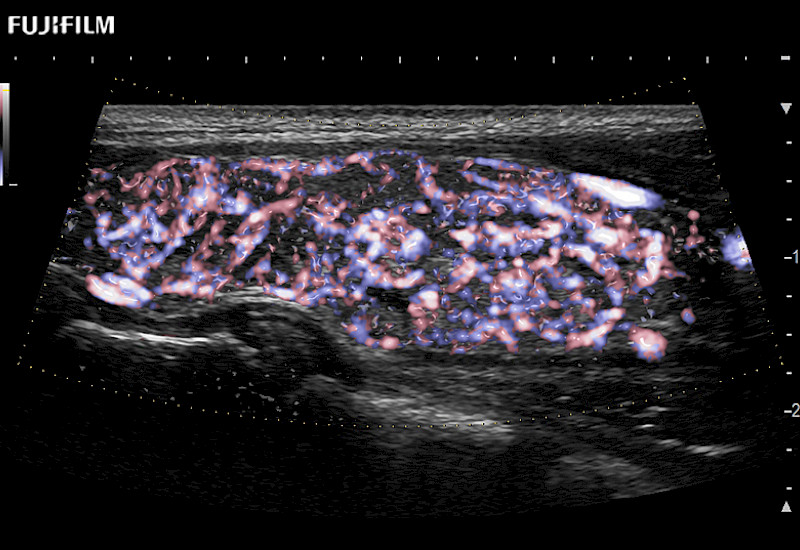

Extraordinary high-resolution digital imaging

Multi-Parametric imaging modalities